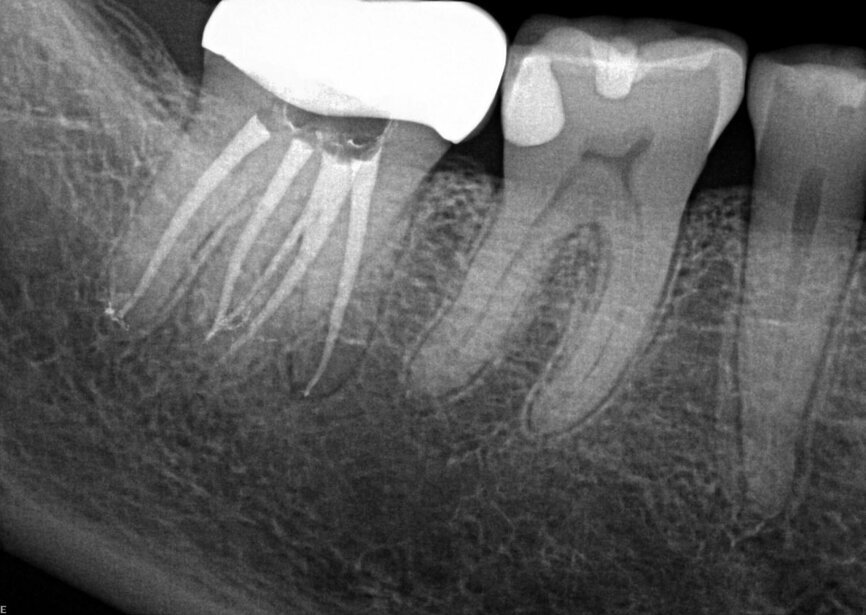

Fig. 14a: Case treated with Bassi Logic controlled memory nickel titanium files. Note the visualization of the third root on this lower molar and conservative canal preparation shape. (Courtesy of Dr. Alex Chan)

Fig. 14b: Case treated with Bassi Logic controlled memory nickel titanium files. Note the visualization of the third root on this lower molar and conservative canal preparation shape. (Courtesy of Dr. Alex Chan)

There are literally dozens of instrumentation systems available globally at this time. One author uses the Twisted File (KavoKerr) (BG) and the other Logic (Bassi Endo) (RM). This notwithstanding, the goals of canal shaping are identical regardless of the system used. Regardless of the instrumentation system used, patency is always sought during canal scouting and instrumentation. Clinicians can debate the relative merits of reciprocation versus rotary motion, optimal Af temperatures (austenite transformation temperatures that control whether a file undergoes the martensitic transformation), controlled memory files ground by CNC machines vs. twisting nickel titanium in R phase along with a multitude of different similar clinical issues. Regardless of these nuances, it is the adherence to basic principles of canal preparation that files create a pathway from coronal to apical to allow irrigant to flow into all of the canal ramifications which clean the root canal system and optimize clinical success.

Goals of canal preparation include keeping the canal centered in its original position within the root structure and keeping the apical foramen at its original position and size. One of the hallmarks of all the cases illustrated is that the apical foramen has been respected. Specifically, it has not been moved, transported, zipped and/or altered in any way. The apical foramen might be thought of as the “North Star” in endodontics. Reaching the apical constriction without transporting the canal and eliminating all debris from the canal and providing a tapering funnel from orifice to apex is a key canal preparation objective.

The final prepared canal shape should be large enough to irrigate and obturate, but not so large as to structurally weaken the tooth. For practical purposes, while treatment philosophies differ, the minimum guidelines for final prepared taper should be .04 and the minimum apical diameter a 30 (depending on the initial size of the foramen). Given the advent of controlled memory nickel titanium there is little indication for larger tapers, especially in fine three-dimensional apical curvatures. As mentioned, patency is essential because its obtainment means that the clinician can always reach the apex during every phase of treatment and its loss means that tissue, toxins and bacteria can remain despite irrigation procedures, especially in the apical third. Apical debris is the harbinger of iatrogenic events including but not limited to canal transportation, zipping, irrigant extrusion and a lack of optimal canal cleaning.